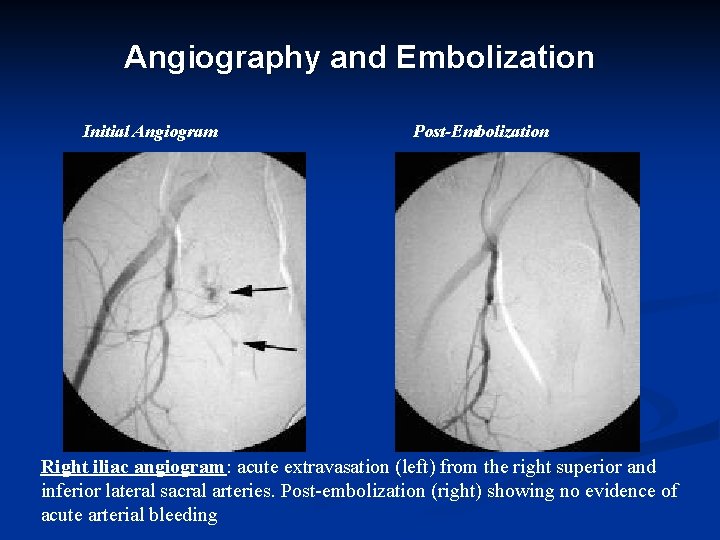

Angiography and Embolization Initial Angiogram Post-Embolization Right iliac angiogram: acute extravasation (left) from the right superior and inferior lateral sacral arteries. Post-embolization (right) showing no evidence of acute arterial bleeding